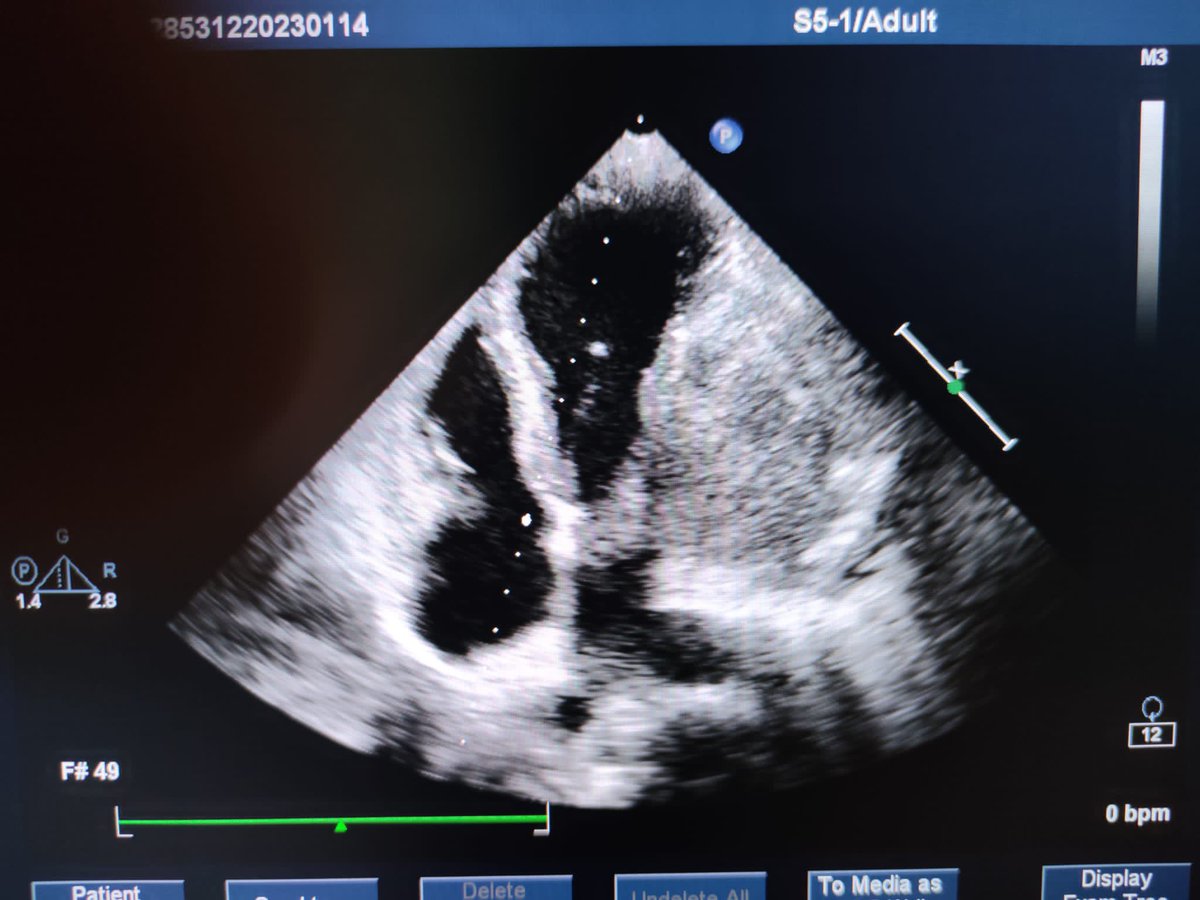

Our editorial @ASE journal. LA strain reservoir strain(LARS) is a sensitive marker of LA dysfunction. LVGLS and LARS are associated with hemodynamic severity of MAC, and are independent predictors of CV outcomes in MAC.bit.ly/47IB9u0 @iamritu @DocStrom @OchsnerCardio @pattypellikka